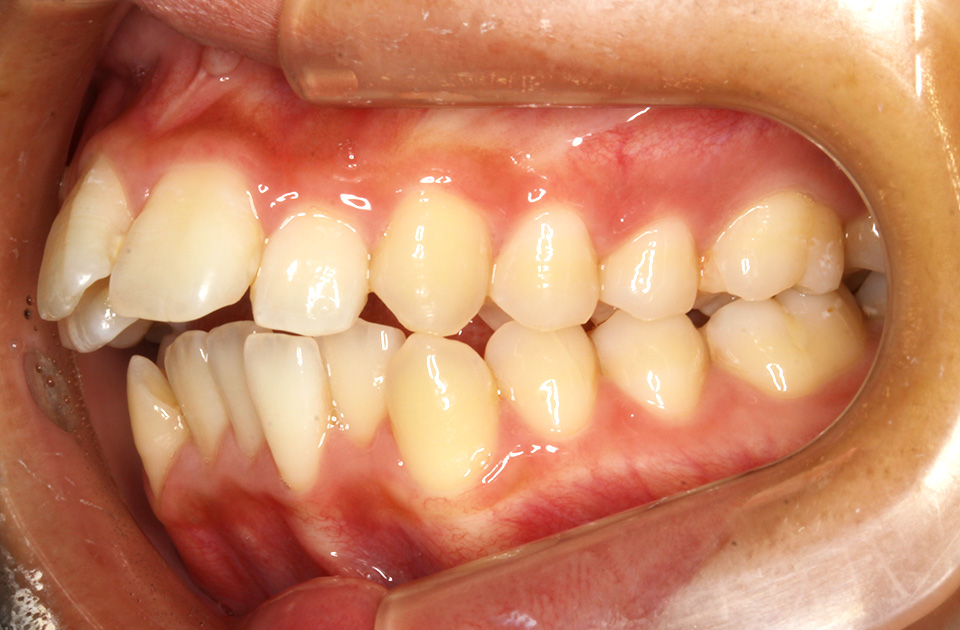

矯正前 右側

矯正後 右側